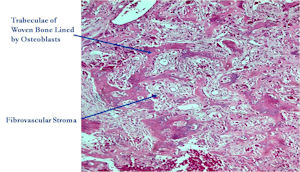

Microscopic Pathology

- Interlacing network of bone trabeculae in a loose fibrovascular stroma

- Prominent vessels

- Osteoblasts are plump, active, scattered mitotic figures

- Osteoblasts line up around periphery of trabeculae (Osteoblastic Rimming)

- Soft tissue component usually surrounded by shell of reactive bone or periosteum (Egg Shell Rim of Calcification)

- No cartilage production (as opposed to osteosarcomas that may contain areas of cartilage)